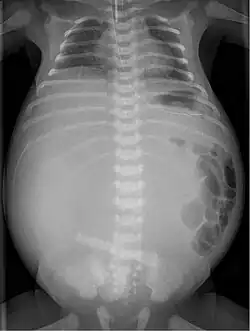

| X-ray of a newborn with meconium pseudocyst resulting from bowel perforation. In this case the cause was atresia of the terminal ileum. There is a fine rim of calcification surrounding the big pseudocyst which shifts the other intestinal structures outwards. | |